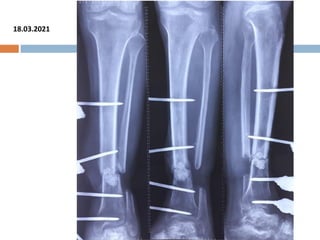

18.03.2021

FOLLOW UP